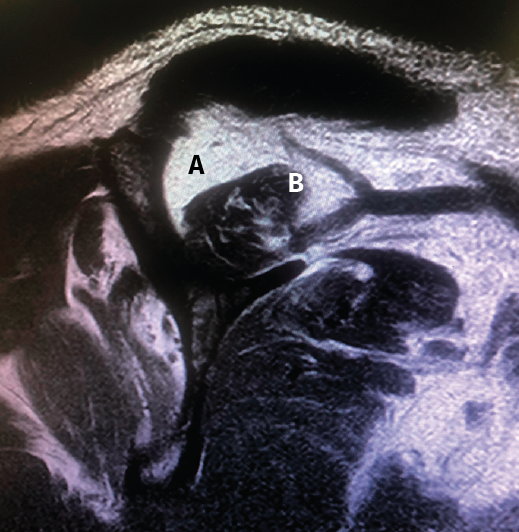

Figura 1. Rotura en forma creciente. A: acromion; B: rotura en forma de semiluna del tendón supraespinoso.

Figura 5. Rotura de tipo C1. A: rotura pequeña de espesor completo del supraespinoso; B: cabeza humeral.